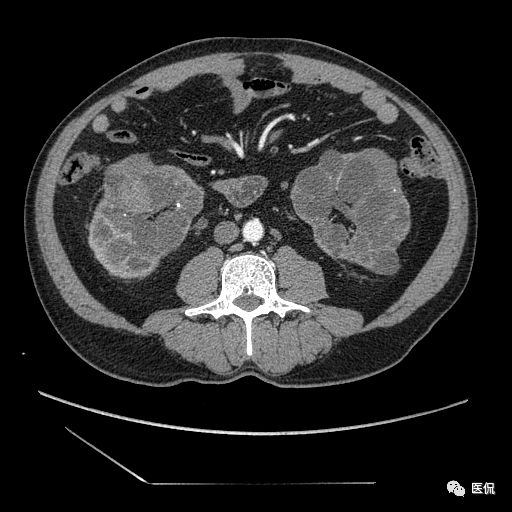

男,年龄:46岁

主诉:肾功能不全20余年,查血肌酐略高于正常,无明显尿频、尿急、尿痛,无肉眼血尿,无明显腰腹部疼痛。查体左肾区叩击痛(-),右肾区叩击痛阳性,双侧输尿管移行区压痛阴性,膀胱区无膨隆,未扪及包块,无压痛。

多囊肾;

双肾实质可见多发囊性密度灶,其内密度不均匀,并可见钙化灶,增强扫描未见明显强化灶。肾周脂肪间隙清晰,与邻近组织分界清楚。

多囊肾的 CT 表现主要表现为双肾增大,轮廓光滑或有分叶,肾实质内多个大小不等的囊肿呈蜂窝状,多呈水样低密度,增强扫描囊肿本身无强化,而囊肿间正常肾组织增强,对比明显。当囊肿张力过高,使囊壁上毛细血管牵拉破裂出血时,表现为囊肿内稍高密度影,随访CT 值减低。囊壁钙化,表现为点线状高密度影像,随访CT值无变化。有文献报道约 30%病例可并发多囊肝或多囊胰。